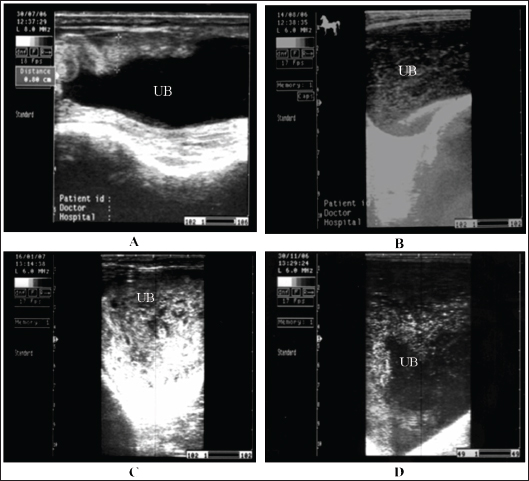

Fig. 18. A sonogram of horses suffering from cystitis showed. Images A and B were obtained from the transrectal window using an 8-MHz linear transducer. Corrugation of the bladder wall (A) and hyperechogenicity of the bladder contents with distal acoustic enhancement (B). Images C and D were obtained from the transrectal window using a 6-MHz transducer. Notice hyperechogenicity of the bladder contents, which leads to acoustic enhancement (C and D). UB=urinary bladder.